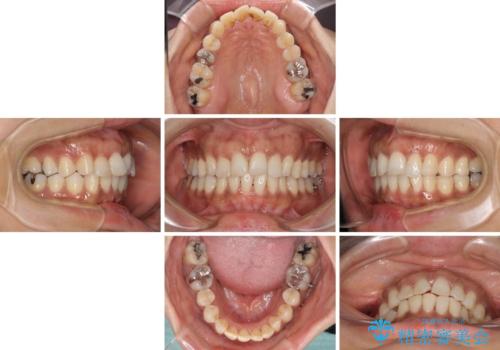

なかなか装着時間が守れず、後戻りを繰り返しながら治療を進めたため、インビザライン治療期間期限ギリギリの5年弱の期間を要しました。